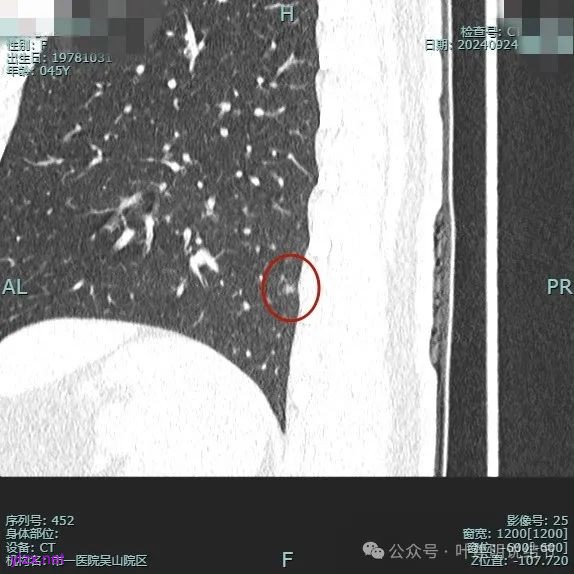

病灶3:

左下叶基底段微小结节,也是混合密度偏实性,瘤肺边界稍不清,与右侧的是类似形态的。

病灶混合密度,但瘤肺边界不够清楚,灶内也不太致密。

整个显得有点模糊,虽有血管进入,但血管说不上显著异常增粗,病灶边缘有细毛刺,贴胸膜近,但缺乏明显收缩力。

病灶显糊,轮廓较清但瘤肺边界欠清晰。

有血管进入,但病灶的感觉总好像缺乏收缩力,也聚拢性不太够。